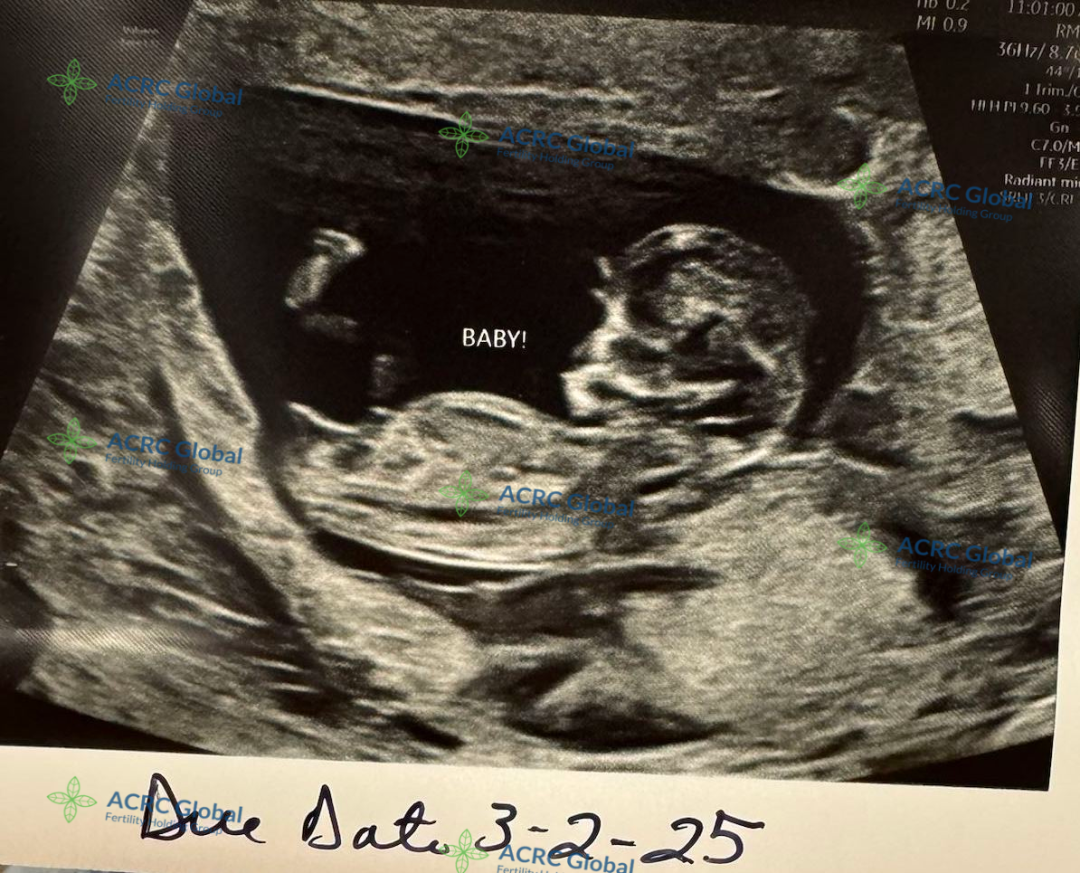

来自伊利诺伊州的爱妈C的第二次孕期旅程也进展顺利,胎宝宝已经进入11周阶段。在这个时候,宝宝已经完成了胚胎期的发育,进入胎儿期,逐渐变得更加稳定。

胎宝宝大约有5厘米长,体重约为7克左右

宝宝的器官和系统正在快速发育,心脏已经开始跳动,神经系统也在形成,B超显示宝宝的手指和脚趾已经开始分开,外耳、鼻子和嘴巴的结构也变得更加清晰。虽然胎宝宝还很小,但此时的他已经开始在羊水中轻微移动,只不过爱妈还感受不到这种活动。